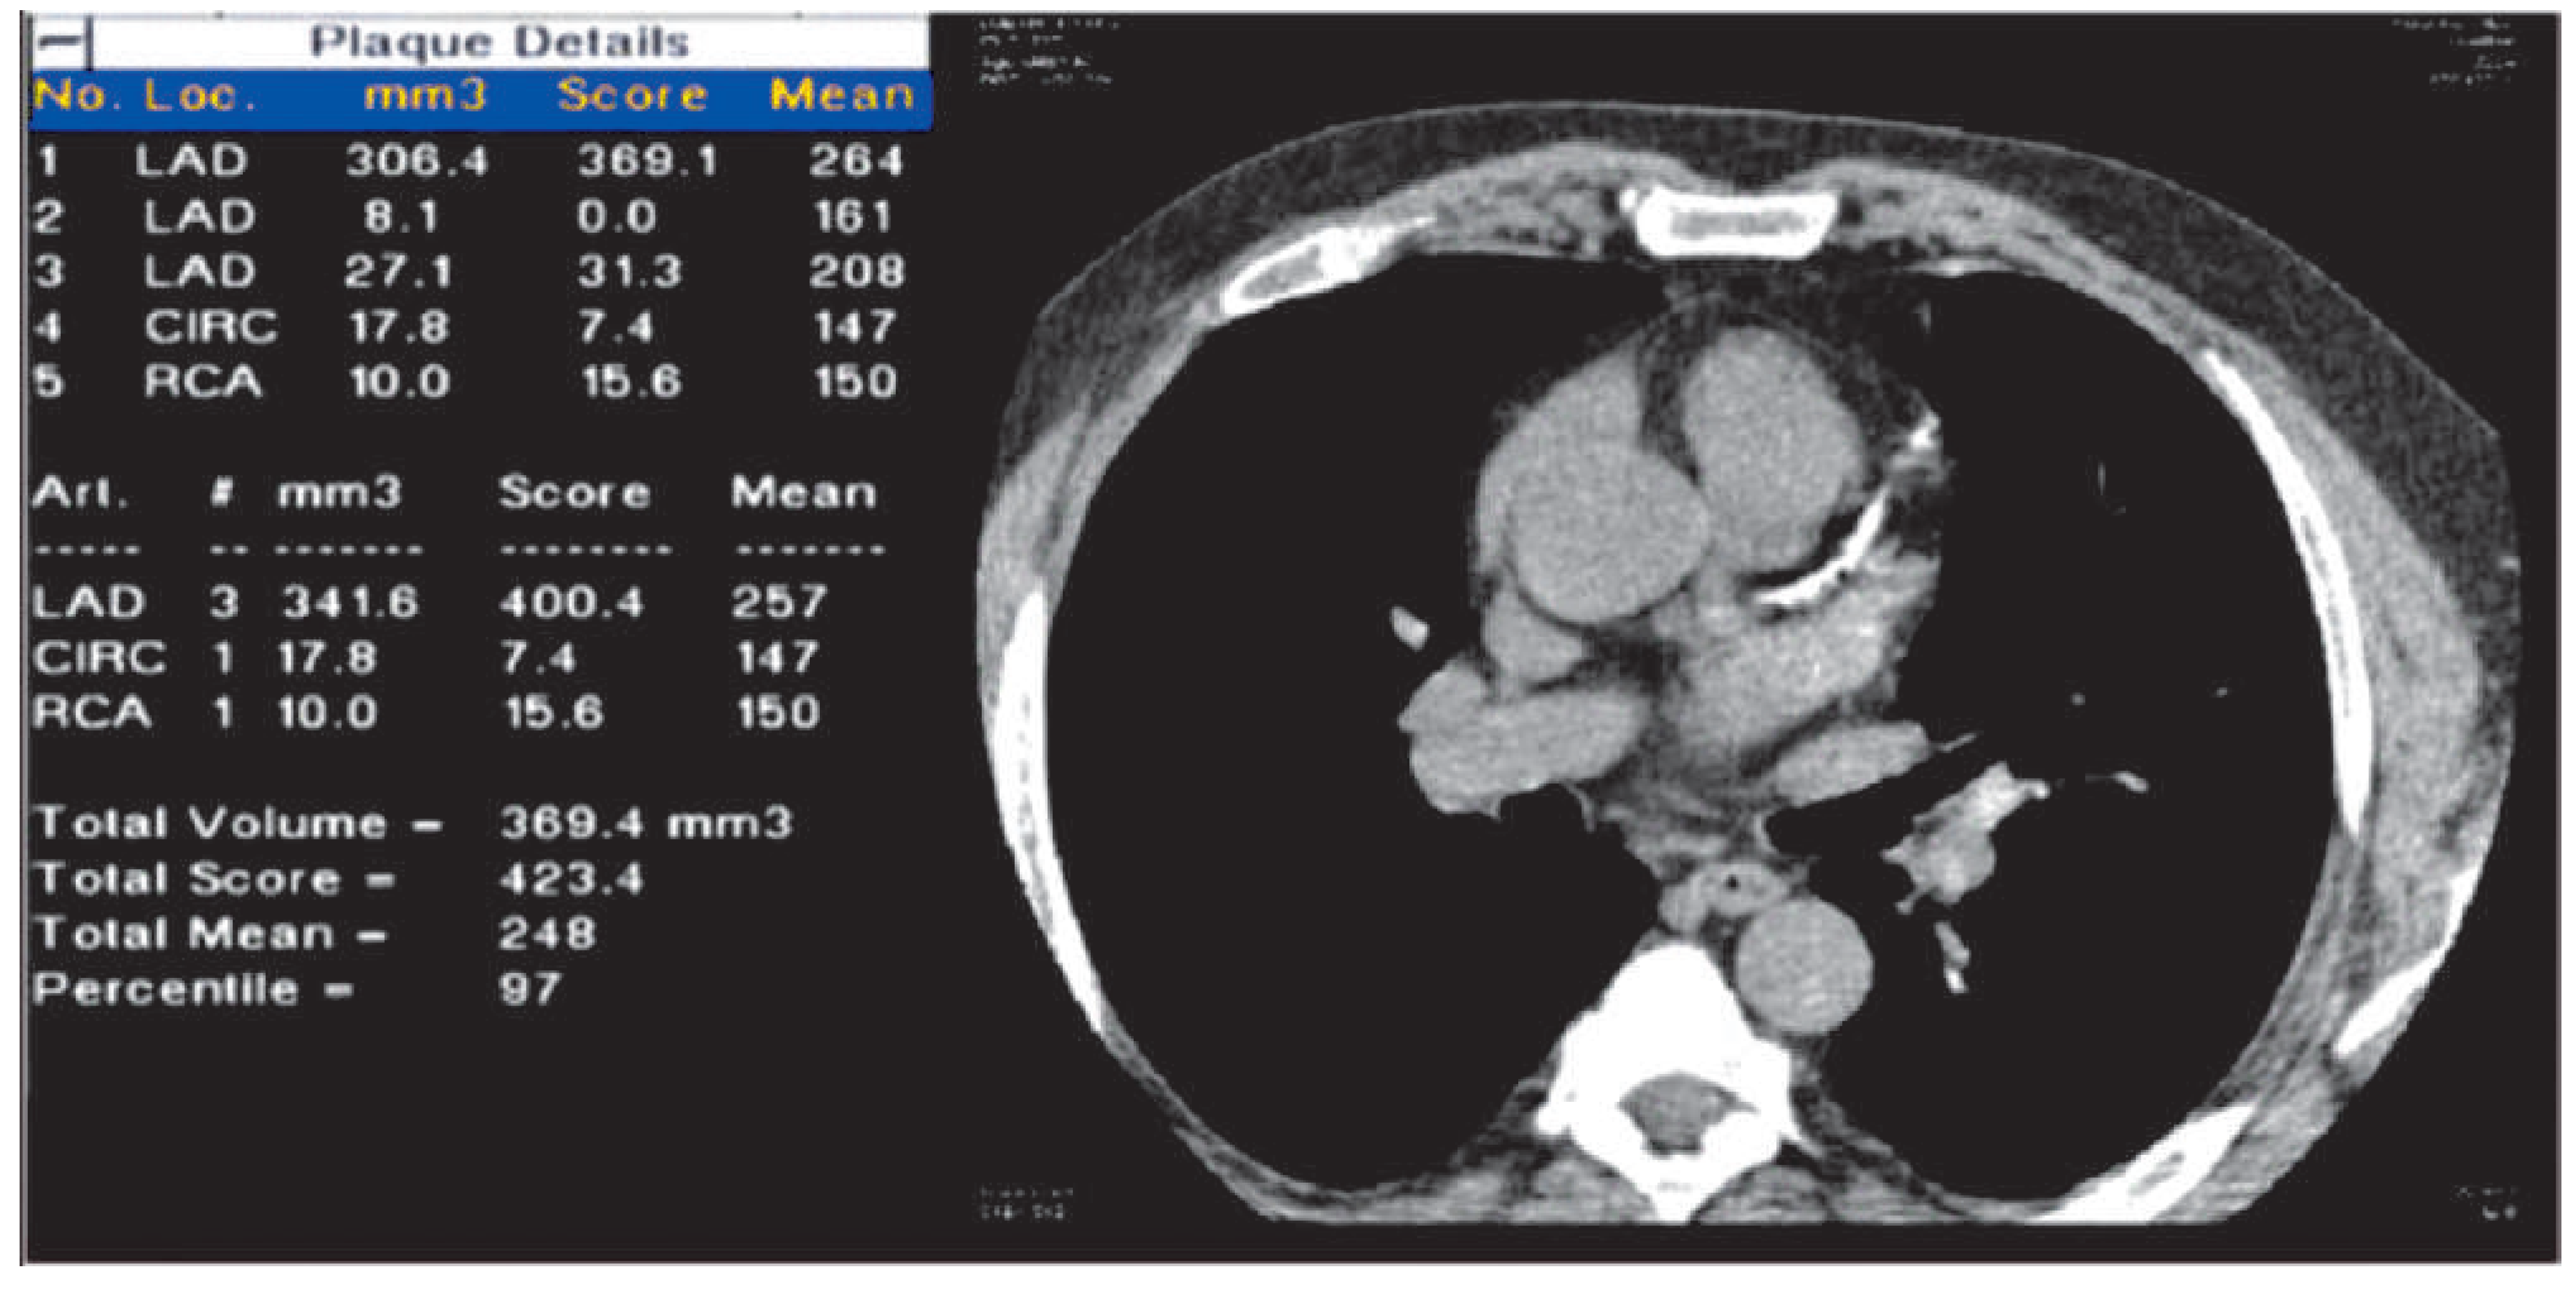

Coronary calcification

Electron beam computed tomography or multislice computed tomography?

Contrast-enhanced coronary imaging with CT